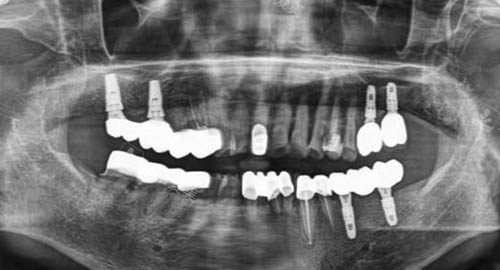

无论是常见的牙齿清洁、补牙,还是较为复杂的牙齿矫正、种植牙等项目,医生们都能凭借可靠的技能为患者提供高质量的服务。